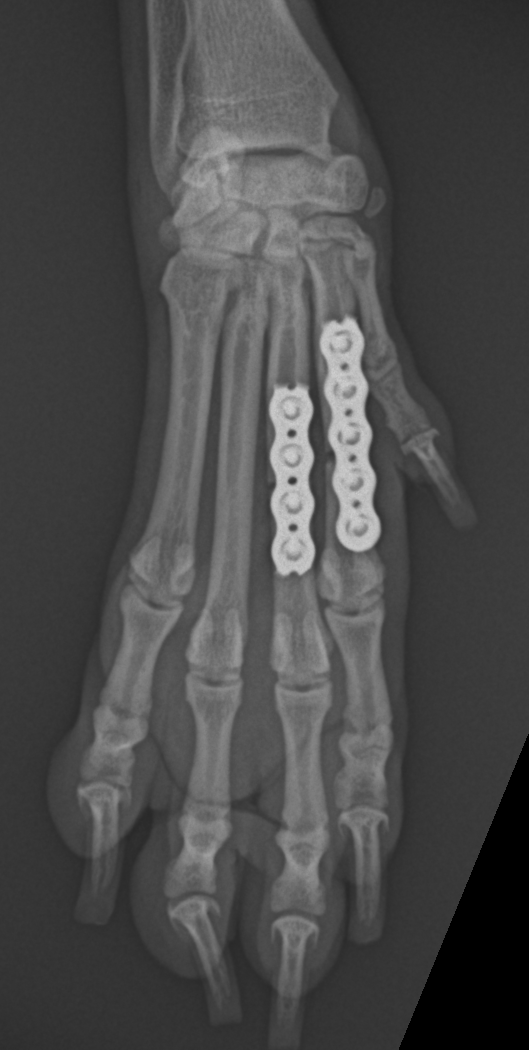

3 金属のプレートを外した場合のメリットとデメリット 31 プレートを外した場合のメリット 311 ①熱や冷えのストレスから解放される 312 ②違和感から解放される 313 ③交通事故のことを思い出す場面が減少する 32 プレートを外した場合のデメリット 321 ①外す前より骨折部分の強度が弱まる 322 ②再度手術する必要がある 4 まとめ15年07月23日 骨折日記 骨折した時に4週間ほどギブス装着との診断。 それなら今日あたりはもう普通に歩けると思っていた単純な私。 そこで友人たちと温泉に行く日を23日の今日に決めていたのだ。 しかし残念なことにまだ松葉杖。 お風呂に松葉杖は図2 骨折型の分類 あった 手 術 療 法 麻酔法は局所麻酔でも可能であるが,術 中の完全な 無痛を考慮し,われわれは腰椎麻酔を用いているタ ーニケット使用下に第5中 足骨基部を中心に弓状切開 にて骨折部を露出する骨折部を整復後径11mmの

手の中手骨 (ちゅうしゅこつ) 骨折 手は人が生活する上で最も使用する頻度の高い身体の一部であり、怪我をしやすい部位です。 手のひらの部分の骨が中手骨で、5本存在します( 図1 )。 中手骨の骨折も日常で良く発生する怪我ですが、骨折しても腫れや変形が目立ちにくいという特徴があります。 中手骨骨折の中でも、骨折する部位によってそれぞれ特徴が

手の中手骨骨折 一般社団法人 日本骨折治療学会 骨折の解説

中手骨骨折 Wikipedia